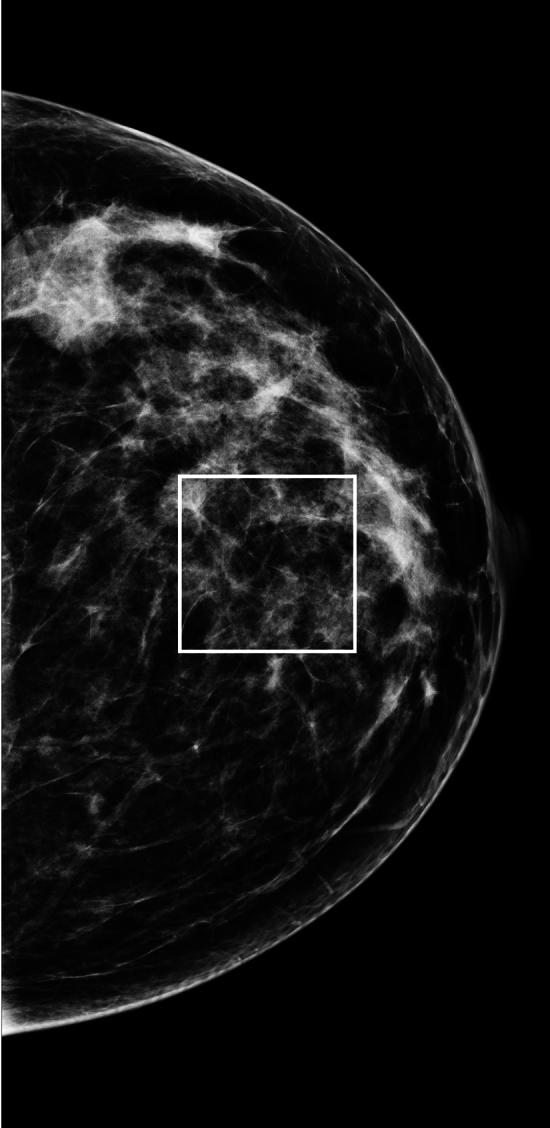

An archetype signal dependent noise (SDN) model is a component used in analyzing images or signals acquired from different technologies. This model-component may share properties with stationary normal white noise (WN). Measurements from WN images were used as standards for making comparisons with SDN in both the image domain (ID) and Fourier domain (FD). The ID wavelet expansion was applied to WN images (n = 1000). Orthogonality conditions were used to parametrically model the variance decomposition, as described in both domains. FD components were investigated with probability density function modeling and summarized measures. SDN images were constructed by multiplying both simulated and clinical mammograms (both with n = 1000) by WN. The variance decomposition for both WN and SDN decreases exponentially as a parametric function of the ID expansion level; expansion image variances for both types of noise were captured similarly in the Fourier plane corresponding with the ID parametric model. The Fourier transform of WN has a uniform power spectrum distributed exponentially; SDN has similar attributes. Fourier inversion of the lag-autocorrelation performed in the FD produced a statistical estimation of the SDN's image factor. These findings are counterintuitive as SDN can be nonstationary in the ID but have stationary attributes in the FD.

一种原型信号相关噪声(SDN)模型是用于分析从不同技术获取的图像或信号的组件。该模型组件可能与平稳正态白噪声(WN)具有共同特性。来自WN图像的测量值被用作在图像域(ID)和傅里叶域(FD)中与SDN进行比较的标准。将ID小波变换应用于WN图像(n = 1000)。如在两个域中所描述的,使用正交性条件对方差分解进行参数建模。通过概率密度函数建模和汇总测量来研究FD分量。通过将模拟乳腺X线照片和临床乳腺X线照片(均为n = 1000)与WN相乘来构建SDN图像。WN和SDN的方差分解均作为ID扩展水平的参数函数呈指数下降;在与ID参数模型相对应的傅里叶平面中,类似地捕获了两种噪声类型的扩展图像方差。WN的傅里叶变换具有呈指数分布的均匀功率谱;SDN具有类似的属性。在FD中执行的滞后自相关的傅里叶反演产生了SDN图像因子的统计估计。这些发现与直觉相反,因为SDN在ID中可能是非平稳的,但在FD中具有平稳属性。